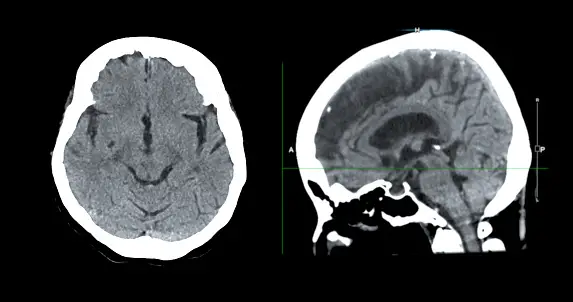

- 컴퓨터 단층촬영(CT): CT는 뇌의 단면 영상을 생성하여 뼈와 같은 뇌 구조의 이상을 확인하는 데 사용됩니다. 종양을 강조하기 위해 대비제를 사용할 수도 있습니다.

최근 뇌종양 진단 분야에서는 혁신적인 기술이 많이 개발되고 있습니다. 이러한 기술은 기존의 진단 방법에 비해 더 정확하고, 비침습적이며, 빠르게 결과를 얻을 수 있습니다. 예를 들어, 자기공명영상(MRI) 검사는 뇌 구조의 상세한 영상을 제공하여 종양의 위치와 크기를 파악하는 데 사용됩니다. 또한, 양전자방출 단층촬영(PET) 검사는 뇌 활동을 영상화하여 종양의 대사적 특성을 평가하는 데 사용됩니다.

## 1. 뇌종양 진단을 위한 혁신적인 기술 혁신적인 영상 기술 자기공명영상(MRI): 뇌종양의 상세한 입체 영상을 제공하여 종양의 크기, 위치, 특성을 정확히 파악할 수 있음. 컴퓨터 단층촬영(CT): 뇌종양의 뼈와 연조직 구조를 시각화하여 종양의 위치와 확산 정도를 평가하는 데 사용됨. 포지트론 방출 단층촬영(PET): 뇌활성을 측정하여 종양 세포의 대사 활동을 검출하고 종양의 악성도를 평가하는 데 사용됨. 분자적 진단 기술 유전자 검사: 뇌종양에서 발견되는 유전자 돌연변이를 식별하여 종양의 유형, 예후, 치료 반응성을 결정하는 데 사용됨. 면역조직화학: 종양 세포의 표면에 있는 특정 단백질을 검출하여 종양의 종류와 특성을 구별하는 데 사용됨. 미세침습적 기술 뇌생검: 종양 조직의 한 부분을 제거하여 종양의 병리학적 진단과 분자적 분석을 위한 검체를 제공함. 액체 생검: 혈액이나 뇌척수액에서 종양 세포나 유전자 물질을 검출하여 비침습적으로 종양 진단과 모니터링을 수행하는 데 사용됨. 기타 혁신적인 기술 인공지능(AI): 의료 영상 데이터를 분석하여 종양을 자동으로 감지하고 특성화하는 데 사용됨. 가상 현실(VR): 외과의사가 수술 중 뇌종양을 시각화하고 제거하는 데 도움이 됨. 3D 프린팅: 환자 맞춤형 수술 가이드 및 임플란트를 제작하여 수술의 정확도와 효과성을 향상시킴.## 1. 최신 뇌종양 진단 기술 최신 영상 진단 기술 자기 공명 영상(MRI): 강력한 자기장과 전파를 사용하여 뇌 내부 구조의 상세한 영상을 생성합니다. 컴퓨터 단층 촬영(CT): X선을 사용하여 뇌의 뼈와 연조직의 단면도를 생성합니다. 양전자 방출 단층촬영(PET): 방사성 동위원소를 주입하여 뇌의 대사 활동을 측정합니다. 분자 영상 기술 MR 분광법(MRS): 뇌의 화학적 프로필을 분석하여 종양과 정상 조직을 구별합니다. 핵의학 영상 기술: 특정 수용체에 결합하는 방사성 표지자를 주입하여 종양의 특성을 파악합니다. 혈액 검사 종양 마커 검사: 뇌종양에서 발견되는 특정 단백질이나 암세포를 탐지합니다. 유전자 검사: 종양의 유전적 특성을 분석하여 맞춤형 치료 계획을 수립합니다. 조직 검사 생검: 종양에서 세포나 조직 샘플을 채취하여 현미경 검사를 통해 종양의 유형과 등급을 확인합니다. 기술적 진보 인공 지능(AI): 영상 분석을 자동화하고 정확성을 향상시킵니다. 가상 현실(VR): 수술 계획과 시뮬레이션을 위한 몰입형 환경을 제공합니다. 3D 프린팅: 환자별 맞춤형 치료 장치 및 모델을 생성합니다. 이러한 기술적 진보는 의료진이 뇌종양을 더 정확하고 신속하게 진단하고 맞춤형 치료 계획을 수립하는 데 도움이 됩니다.